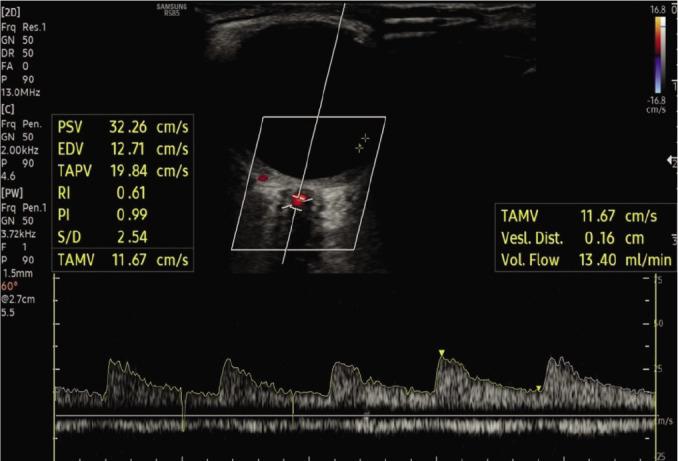

The study was planned prospectively. The data of patients with AS were compared to those of age- and gender-matched healthy volunteers. A total of 42 participants, 23 (54.8%) males and 19 (45.2%) females, with a mean age of 42.4±12.6 years were included in the study. In addition to demographic information, such as age and gender, the diameter, peak systolic velocity, end-diastolic velocity, mean velocity, resistive index, pulsatility index, and blood flow volumes of the central retinal artery of the left eye were measured using spectral Doppler ultrasonography.

According to the comparison of the patients with and without AS according to orbital Doppler ultrasonography findings, the mean velocity, resistive index, and volume measurements of the patients with AS were significantly higher than those without AS (p=0.028, p=0.039, and p=0.038, respectively). However, in the subgroup analysis of the AS group, the Doppler findings did not significantly differ between the patients with and without anterior uveitis.

In the patient group with AS, independent of anterior uveitis (AU), there was a difference in Doppler parameters and therefore in ophthalmic vasculature. In patients with AS, orbital vascularity changes can be detected with orbital Doppler US before clinical signs appear.